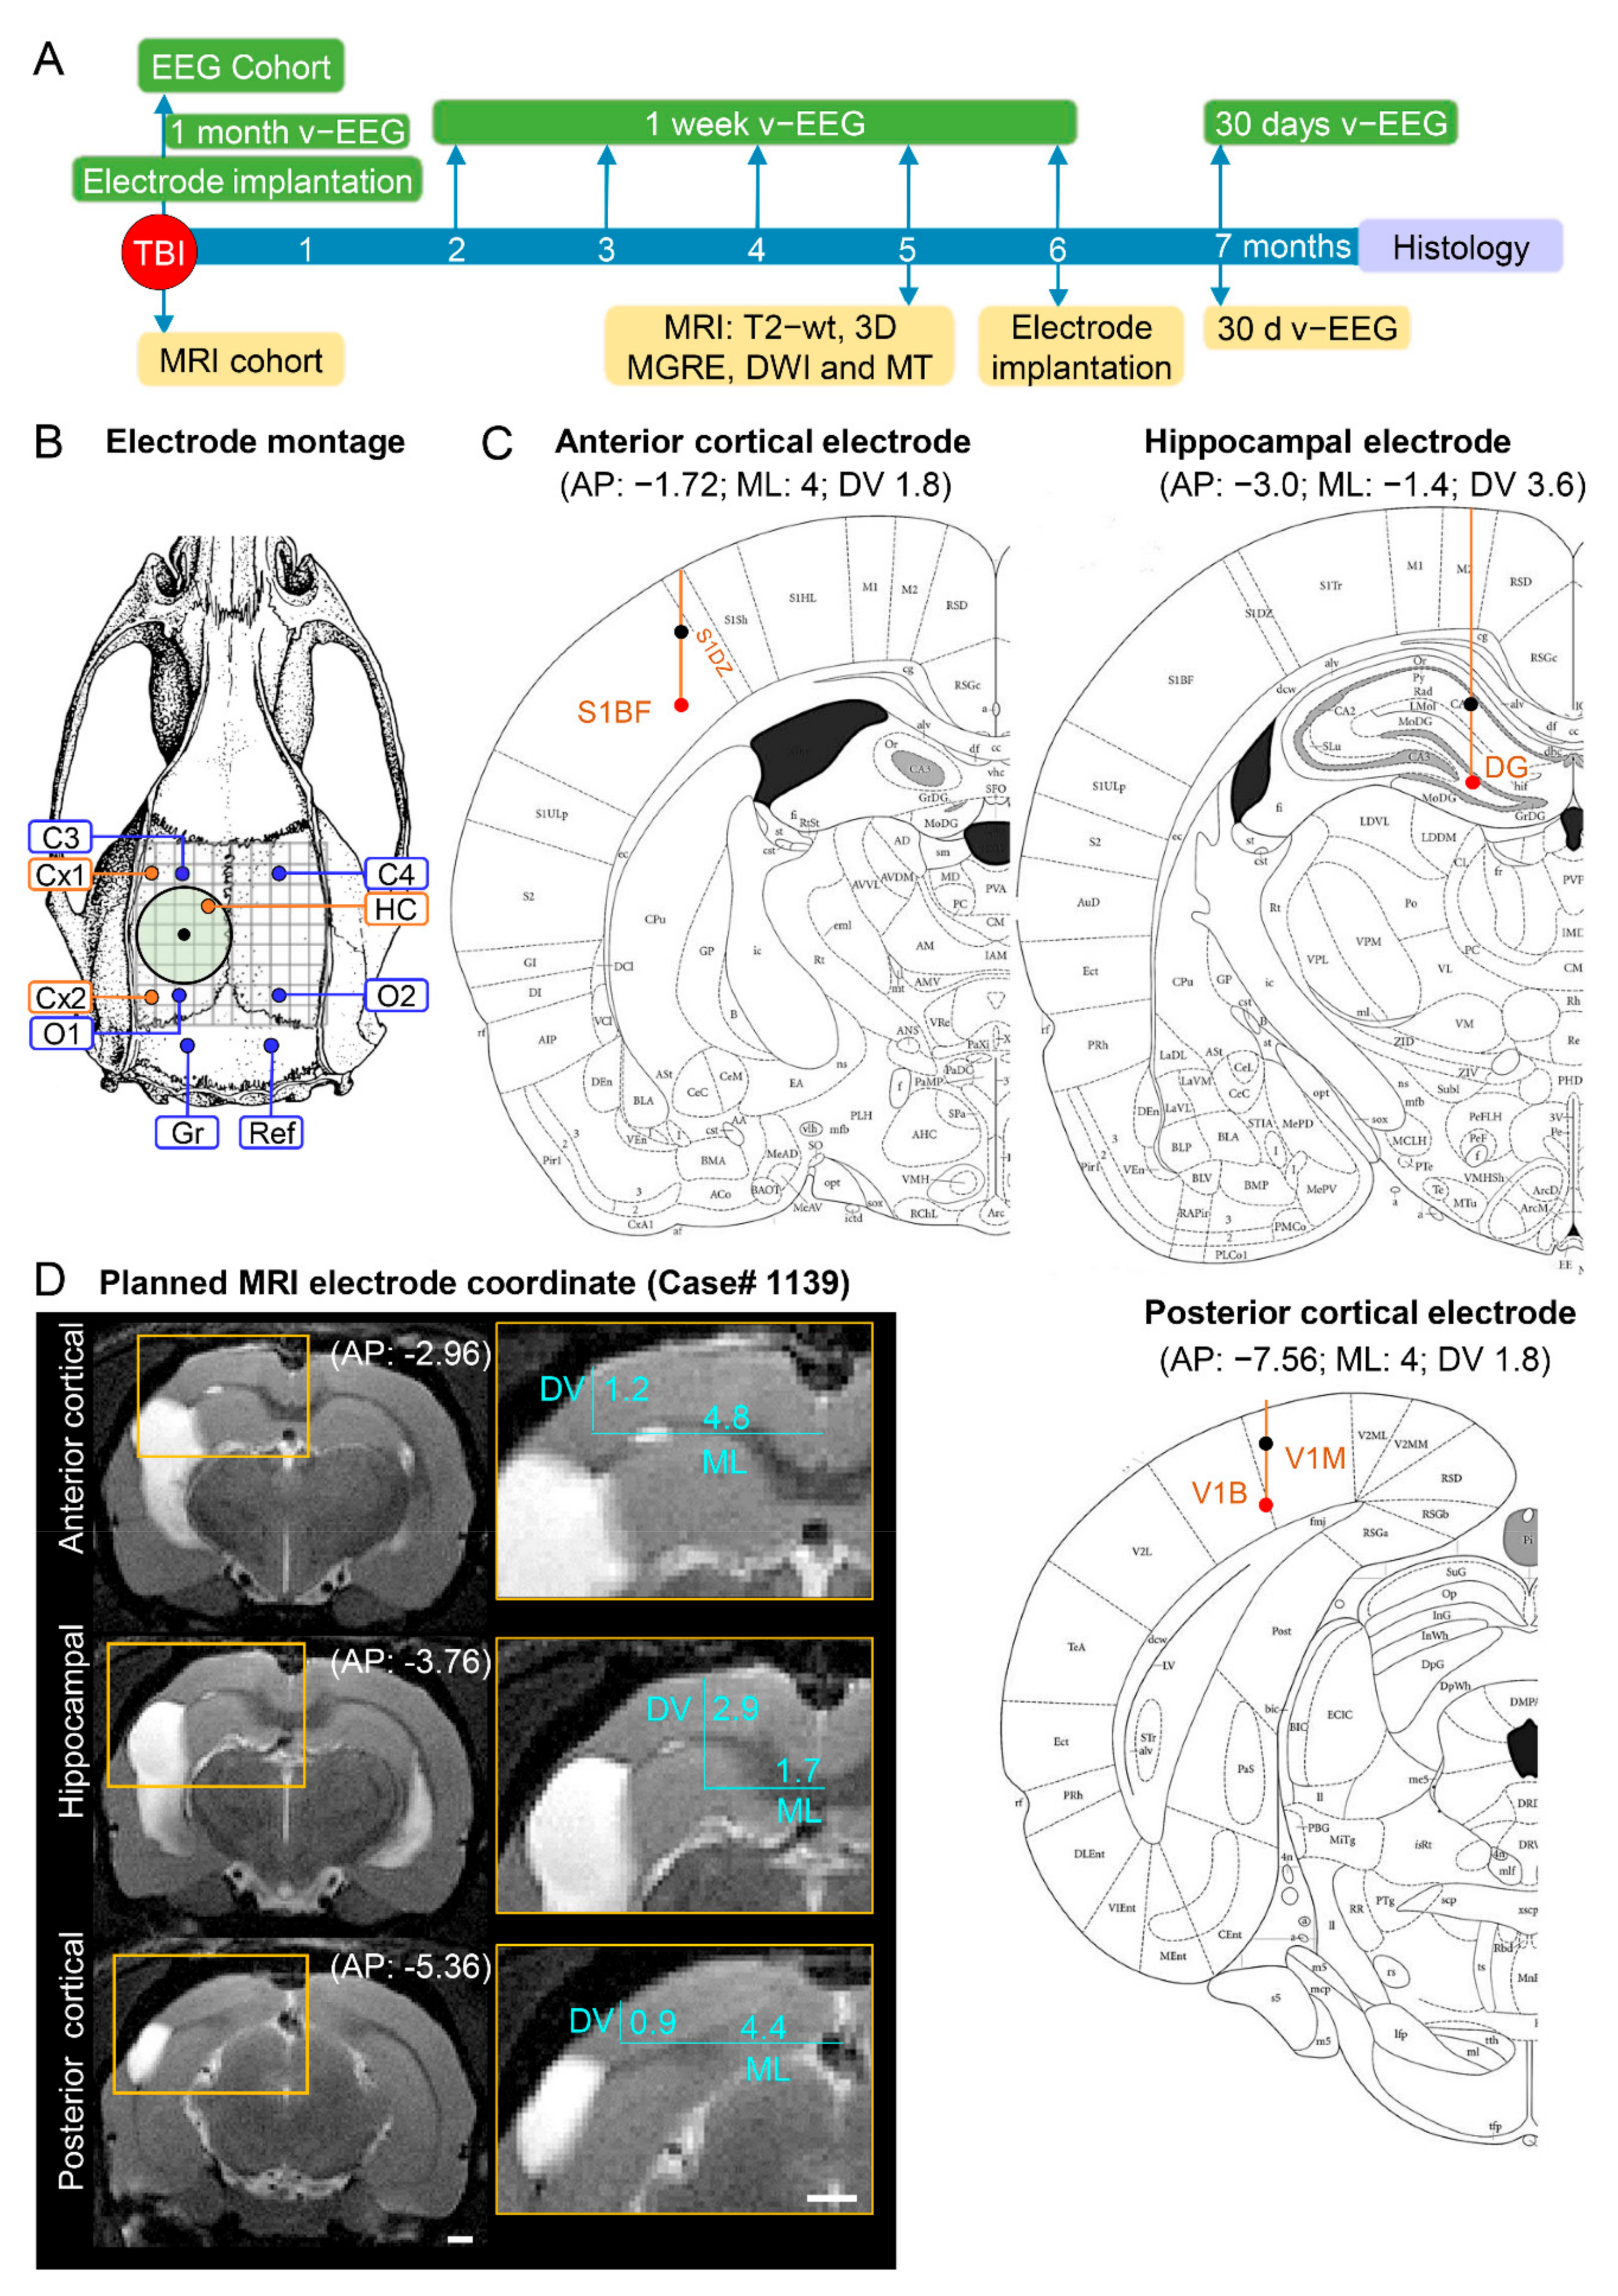

Study design (Figure 1). The study design, randomization, and interventions performed in the 2 study cohorts are summarized in Figure 1. The rats were divided into EEG (14 sham, 43 TBI) and MRI (11 sham, 31 TBI) cohorts. In the EEG cohort, electrodes were implanted immediately after the induction of lateral FPI. Starting immediately after the TBI, video-EEG was performed first for 1 month and then during the 1st week of months 2 through 6. In the 7th post-TBI month, the rats underwent a 24 h/7 days video-EEG to record unprovoked spontaneous seizures (i.e., confirm epilepsy diagnosis). In the MRI cohort, the rats were imaged at 2, 9, and 30 days and at 5 months post-TBI; electrodes were implanted 14.02 ± 1.34 days (range: 4–40 days) after the last MRI, and video-EEG monitoring was performed during the 7th post-TBI month to detect unprovoked seizures (Figure 1A). Both groups were killed at the end of the 7-month follow-up, and the brains were processed for ex vivo MRI and histological analysis (Figure 1).

Figure 1.

Study design, electrode montage, and atlas or MRI-planned electrode coordinates. (A) Study design. Following TBI, rats were divided into either the EEG or MRI cohort. The rats of the EEG cohort were implanted with electrodes after fully righting themselves following induction of TBI. The rats were followed up immediately afterward with 1 month video-EEG and then for 1 week monthly until the 6th post-TBI month. The rats of the MRI cohort were magnetic resonance-imaged at 5 months post-TBI and T2-wt images were used to calculate the coordinates of the intracerebral electrodes implanted at 6 months post-TBI. Both cohorts were continuously monitored with video-EEG for 30 days at 7 months post-TBI to diagnose epilepsy. At the end of the 7-month follow-up period, all rats were euthanized and the brains processed for histological identification of the location of the intracerebral electrodes. (B) Electrode montage used in the study. Four epidural screw electrodes (C3, C4, O1 and O2), 3 intracerebral bipolar wire electrodes (anterior cortical Cx1, posterior cortical Cx2, and hippocampal HC), a ground (Gr) and reference (Ref) electrode. (C) Atlas plates demonstrating the planned coordinates used in the EEG cohort to implant the anterior cortical, hippocampal, and posterior cortical electrodes. The black dot refers to the upper tip and the red dot to the lower tip of the bipolar electrode (1 mm apart). Reprinted/adapted with permission from [25]. 2007, Elsevier Inc. (D) MRI T2-wt images of rat 1139 demonstrating the planned-MRI coordinates of the intracerebral anterior cortical, hippocampal, and posterior cortical electrodes. The anteroposterior (AP) coordinate was determined by aligning the MR images with the atlas [25]. The mediolateral (ML) and dorsoventral (DV) coordinates were determined using ImageJ software (version 1.47v, Wayne Rasband and contributors, National Institute of Health, USA).

EEG cohort. Electrodes were implanted immediately after the lateral FPI using coordinates based on a rat brain atlas (Figure 1B,C) [25]. In brief, after return of the righting reflex, the rat was reanesthetized with isoflurane and placed in a stereotaxic frame. Four recording epidural stainless-steel screw electrodes (EM12/20/SPC; P1 Technologies, Roanoke, VA, USA) were implanted into the skull: 2 ipsilaterally (frontal cortex; C3, AP: −1.7, ML: left 2.5 and parieto-occipital cortex; O1, AP: −7.6, ML: left 2.5) and 2 contralaterally (frontal cortex; C4, AP: right 1.7; ML: −2.5 and parieto-occipital cortex; O2, AP: −7.6; ML: right 2.5; Figure 1B). Three intracerebral tungsten bipolar recording electrodes (EM12/3-2TW/SPC; P1 Technologies.; Ø 0.5 mm, tip separation 1.0 mm) were implanted ipsilaterally in the anterior perilesional cortex (AP: −1.72; ML: −4.0; DV: 1.8), septal hippocampus (AP: −3.0; ML: −1.4; DV: 3.6), and posterior perilesional cortex (AP: −7.56; ML: −4.0; DV: 1.8; Figure 1C). In addition, 1 epidural screw electrode serving as a ground was placed ipsilaterally posterior to lambda, and another serving as a reference electrode was placed contralaterally. Atlas-based placement of electrodes relies on calculating the target coordinates based on fixed skull surface landmarks, i.e., identification of bregma and midline sutural landmarks. Thus, the coordinates are defined independently of the intracranial changes in brain volume and orientation, which progress over time after TBI.

MRI cohort. Electrodes were implanted approximately 6 months (164 ± 1.4 days, range: 156–195 days) post-TBI. The locations of the epidural recording screws, ground, and reference electrodes were the same as in the EEG cohort described above. Due to progressive brain atrophy and ventricle enlargement, we first assessed the severity of cortical and hippocampal atrophy in each rat on MRI T2-weighted (T2-wt) images to define the AP, ML, and DV coordinates to avoid electrode misplacements (see below) (Figure 1D). Based on the analysis, the distance between the tips of the bipolar electrodes was reduced from 1.0 mm to 0.5 mm to fit within the atrophied cortex (upper tip in layer I, lower tip in layer V) or hippocampus (upper tip in CA1, lower tip in hilus).